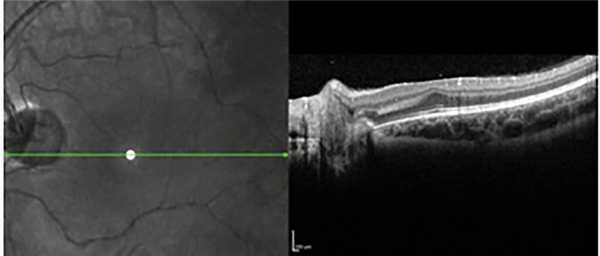

Оптическую когерентную томографию (ОКТ) проводили с помощью прибора Spectralis HRA+OCT («Heidelberg Engineering», Germany).

(6 глаз) и с выраженной сосудистой активностью в заднем полюсе глаза и образованием сосудистых аркад и анастомозов на границе с аваскулярной сетчаткой (18 глаз). Однако при этом типе заболевания рост экстраретинальной пролиферации отмечался на границе с аваскулярной сетчаткой и можно было проследить стадийность процесса. Геморрагический компонент присутствовал, как правило, на границе с бессосудистой сетчаткой. По данным ОКТ отмечалось наличие формирующейся фовеолярной депрессии, причем на фоне выраженной сосудистой активности с наличием экстраретинальной пролиферации на границе с аваскулярной сетчаткой, что свидетельствует о большей степени «зрелости» сетчатки и отсутствии патологического процесса в макуле на ранних стадиях РН (рис. 6). Рисунок 6. Результаты ОКТ: формирующаяся фовеолярная депрессия при передней РН первой зоны.

Результаты проведенной ОКТ показали, что у глубоко недоношенных детей с благоприятными исходами РН на 33 (61%) из 54 глаз отмечалось нарушение анатомического контура макулы. На 12 глазах с остаточными изменениями I—II степени сглаженность фовеолярного контура в совокупности с сохранностью эмбрионального строения макулы (слоев нейроэпителия в фовеа) свидетельствовала о нарушении дифференцировки макулы вследствие недоношенности, и лишь на трех глазах она сопровождалась снижением остроты зрения ниже 0,3. На 10 глазах со II степенью РН сглаженность фовеолярного контура сопровождалась наличием структурных изменений (кистовидный отек и тракционная деформация нейроэпителия), невидимых при офтальмоскопии, что и объясняло некорригируемое снижение остроты зрения. При III степени РН сформированный фовеолярный контур и сохранность слоев нейроэпителия в макуле выявлены только на двух глазах. В остальных случаях фовеолярный контур был сглажен или отсутствовал вследствие тракционной деформации макулы после перенесенной РН и коррелировал со сниженной остротой зрения (рис. 7).

Рис. 7. Сглаженный фовеолярный контур и тракционная деформация сетчатки на глазу с рубцовой РН III степени.